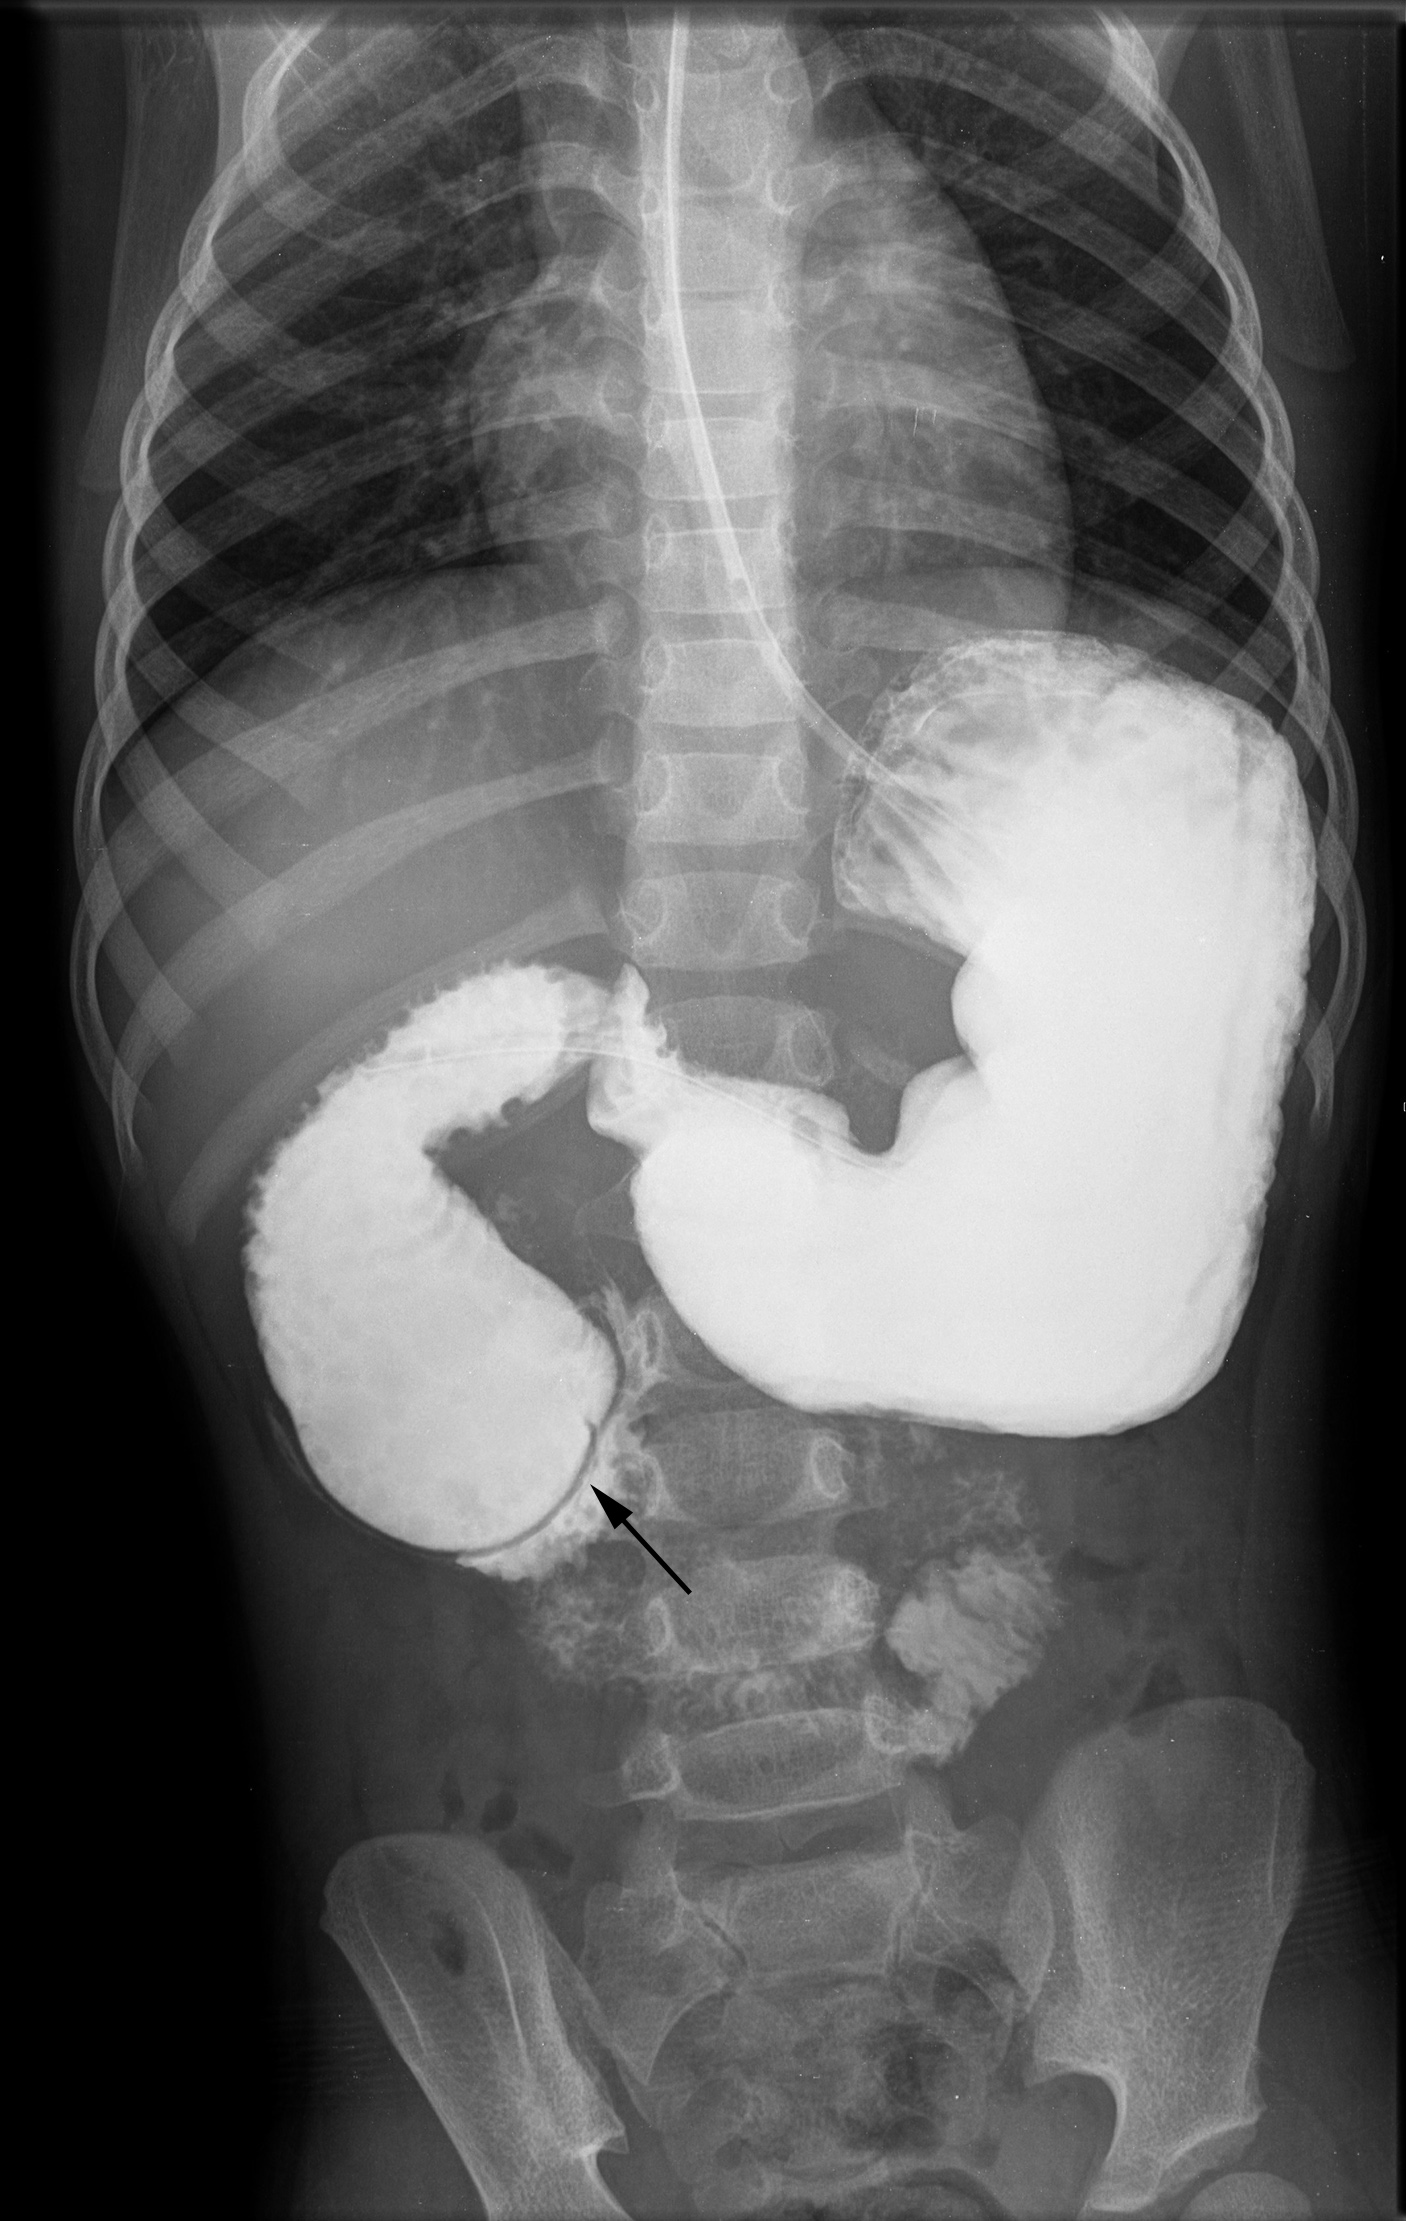

A obstrução duodenal congénita, secundária a atresia ou estenose, tem tipicamente apresentação no período neonatal com sinais de oclusão intestinal alta. Todavia, uma apresentação mais tardia e diversa pode ocorrer nos raros casos de obstrução parcial do duodeno devido à presença de uma membrana duodenal perfurada, colocando sérios desafios no seu diagnóstico.Reportam-se três casos clínicos de obstrução duodenal congénita com apresentação após o período neonatal. Os três casos partilham uma história de vómitos recorrentes e má progressão ponderal com início após a diversificação alimentar. A identificação de achados radiológicos específicos, tais como os sinais de dupla bolha e de wind sock, foi determinante para o diagnóstico.A obstrução duodenal congénita devido à presença de uma membrana duodenal perfurada é uma entidade rara e o seu reconhecimento nem sempre imediato. Uma história clínica minuciosa, aliada a achados radiológicos específicos, constitui a chave para um diagnóstico atempado dos casos de obstrução duodenal congénita com apresentação tardia.